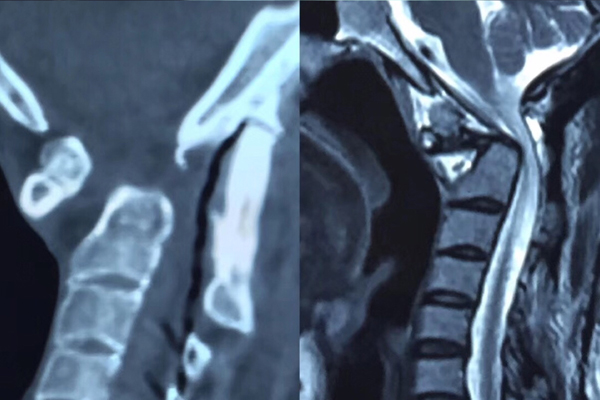

术前CT及磁共振

术后CT及磁共振